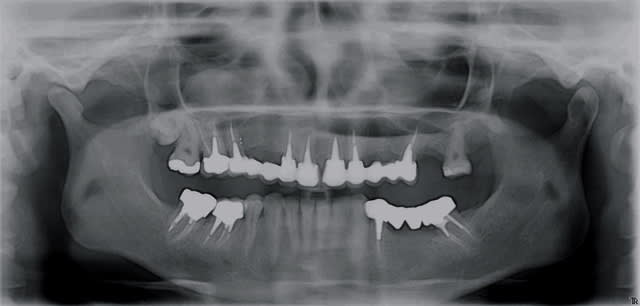

Patiente porteuse d'un bridge de + 10 ans réalisé par un confrère. Celui-ci ayant quitté la région, je la suis depuis peu.

Le bridge est pas trop mal, aucune raison de le déposer pour le moment. La patiente ne le souhaite pas pour le moment, malgrès un esthétisme améliorable. Maintenance parodontal bien suivit.

J'ai dût extraire 26 (carie+++ sous une couronne unitaire)

Comment la remplacer ?

A l'OPT j'ai 4 mm

Au scan c'est confirmé

J'ai réalisé une fenêtre aux niveau des "apex" de 26 pour soulever la membrane et mettre du biomat.

Implant et vis de cica dans la foulée (couple >à 50N obtenue sous forant) (Nobel Replace Speedy WP 5*10mm)

Question: pourquoi à l'OPT l'implant parait toujours plus mésial ?

ps: le polype à droite (asymptômatique) semble venir de la 18 qui est complétement dans le sinus (au scan) ou de 16 mais les canaux semblent obturés à l'apex